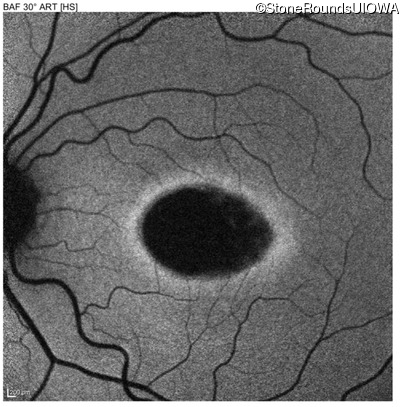

This 22 year old man had macular abnormalities noted incidentally at a routine eye exam at age 19. Since then, he has experienced a gradual loss of acuity particularly in the left eye.